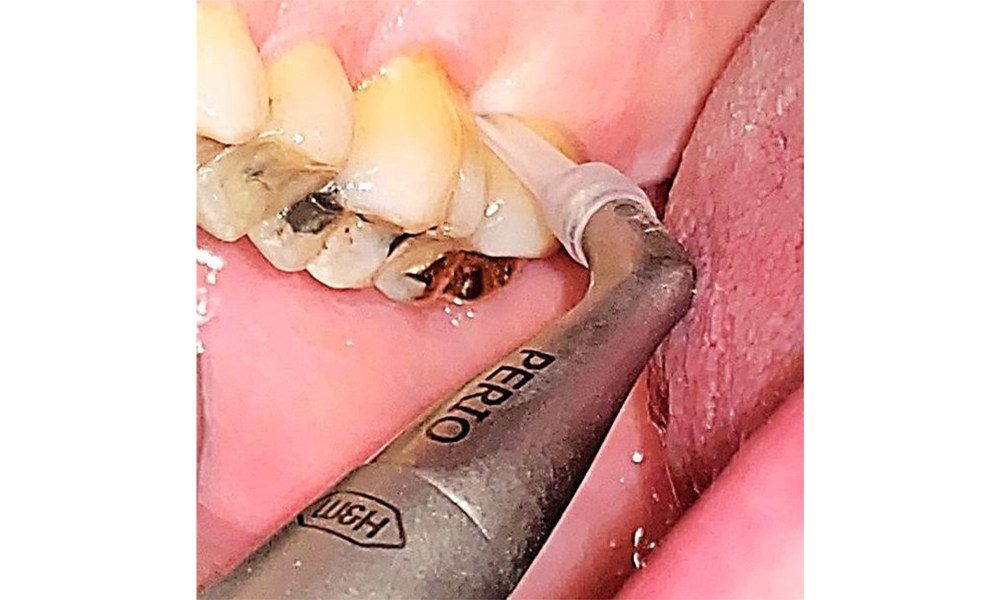

Probing to document the findings in tooth 27 mesiopalatal. © Dr R. Krapf

Fig. 8: Probing to document the findings in tooth 27 mesiopalatal. © Dr R. Krapf

The documentation of periodontal findings, including pocket depth probing and bleeding status, is mandatory during each dental appointment due to the presence of periodontitis (Fig. 8). This will record the individual therapeutic needs and facilitate a rapid response to any progression of the pre-existing periodontitis.